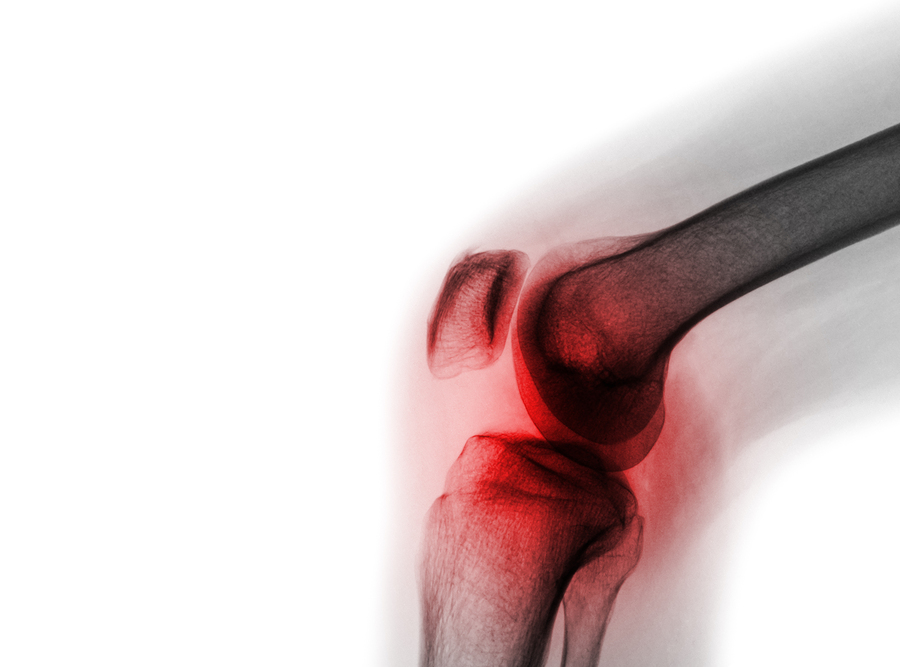

If you have ever experienced severe knee pain, you know there is nothing like it. This kind of pain can put Strongsville Oh residents out of commission, making it hard to enjoy the things you once loved. Thankfully, there are a few things you can do for Knee Pain Treatment Strongsville Oh